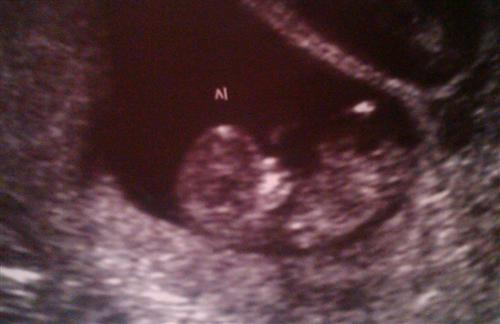

BABY A-11 Weeks

Thank you, Chris!!!

Posted by Wishing4ababy 4/2/11 8:06PM

So happy for you! Congrats again!

Posted by chrisnjoe8108 4/2/11 6:58AM